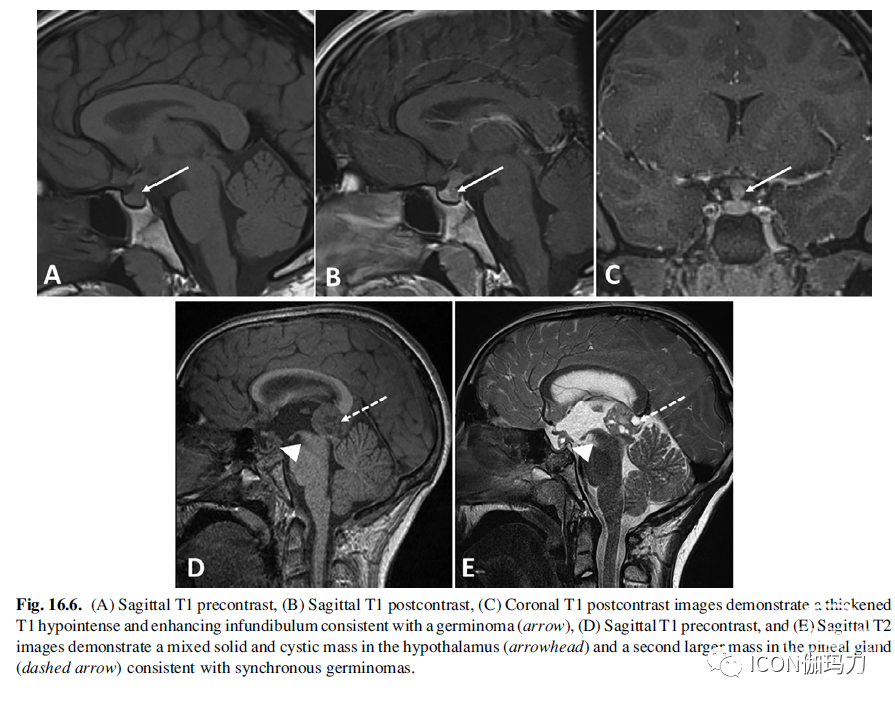

影像学表现可显示漏斗部增厚或下丘脑或漏斗部出现肿块(Saeki et al., 1999)。典型的影像学特征包括第三脑室漏斗部或底部有清晰可见的固体肿块,相对于灰质,T1加权序列为等/低信号,T2加权序列为等/高信号(图16.6)。PPBS在大多数患者中不存在,但有多达20%的患者保留了PPBS。它们表现出明显的均匀强化。可见T2高信号区,反映囊性或坏死灶。不常见的是T2低信号灶,反映出血。可发生脑脊液播散和实质浸润。因此,对整个神经轴的成像至关重要。生殖细胞瘤可能在影像学发现明确异常或非特异性漏斗部增厚之前就在临床出现,这可能导致对特发性CDI的最初错误分类。在这种情况下,必须进行系列随访成像,以评估生殖细胞瘤的演变变化。

图16.6.(A)矢状位T1平扫,(B)矢状位T1增强,(C)冠状位T1增强图像显示与生殖细胞瘤一致的增厚的T1低信号和漏斗部强化(箭头),(D)矢状位T1平扫,(E)矢状位T2图像显示下丘脑(箭头)有一个混合实性和囊性肿块,松果体(虚线箭头)有第二个更大的肿块,与同时存在的生殖细胞瘤一致。